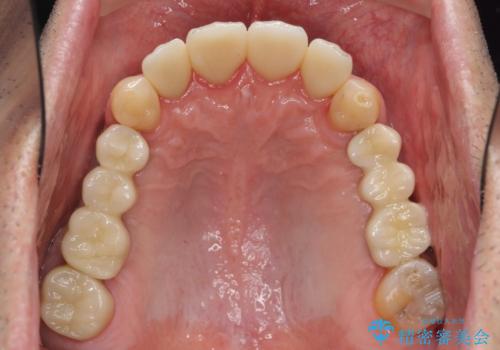

インプラント治療・セラミック治療を含む 全顎的虫歯治療

- 「 仕事が忙しく、虫歯を放置しすぎてしまった。この際全てきっちりと治したい。」と来院されました。

・歯の欠損

・虫歯

・深い虫歯

・欠損の放置による対合歯の挺出

・咬合平面の乱れ

・感染根管

以上のような問題を、徹底的な虫歯治療、歯周外科、インプラント治療、部分矯正治療、精密根管治療を用いてひとつずつ解決ししっかりと長期的に食事を楽しめるような口腔内環境の再構築を目指します。